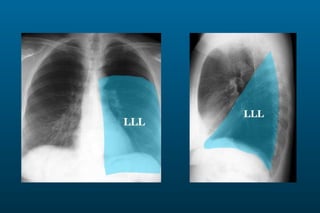

1) The posterior-anterior (PA) view is the standard and most reliable technique for a chest x-ray. It allows detection of air under the diaphragm. 2) A lateral view helps localize infiltrates and evaluate the cardiomediastinal silhouette, effusions, and left atrial dilation. 3) An anterior-posterior (AP) view is used when a patient is too ill to be transported, but image quality is poorer and structures may appear enlarged compared to a PA view.